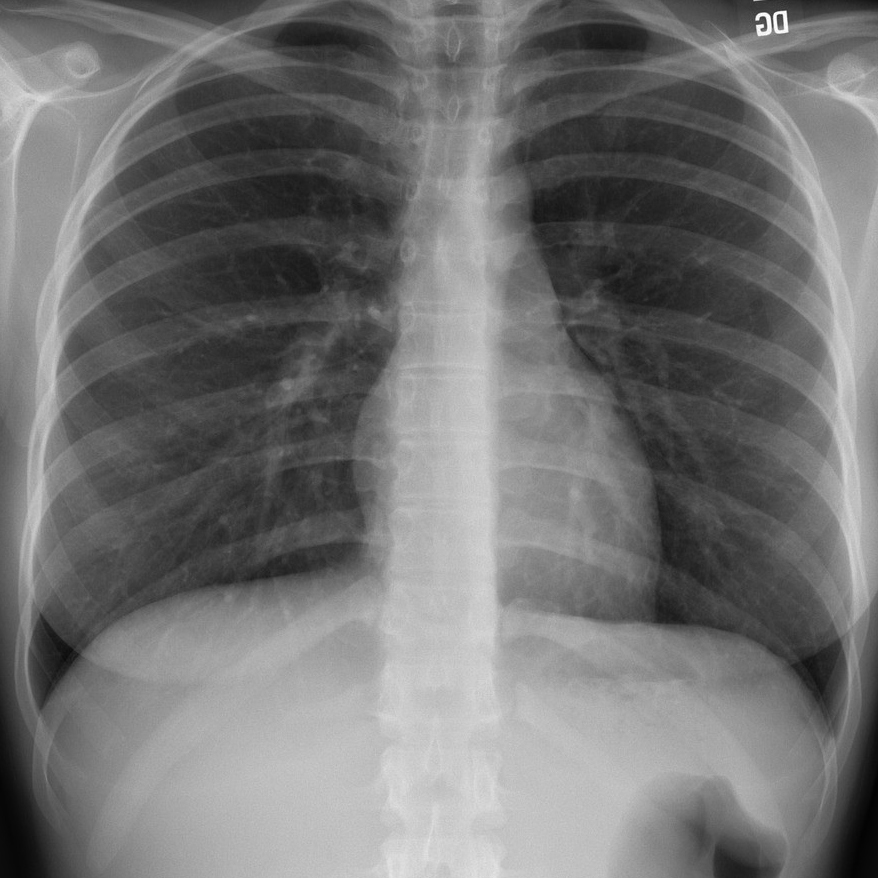

Figure 6 presents image examples for each class retrieved from the RYDLS-20 database. It is worth to mentioning that we have no further information concerning the CXR images with regarding the CXR machine used to take the image, as well as the origin, age and ethnicity of the people whose these images belong to.

Refer to caption

(a) Normal.

(b) COVID-19.

(c) SARS.

(d) MERS.

(e) Pneumocystis.

(f) Streptococcus.

(g) Varicella.

Figure 6: RYDLS-20 image samples.